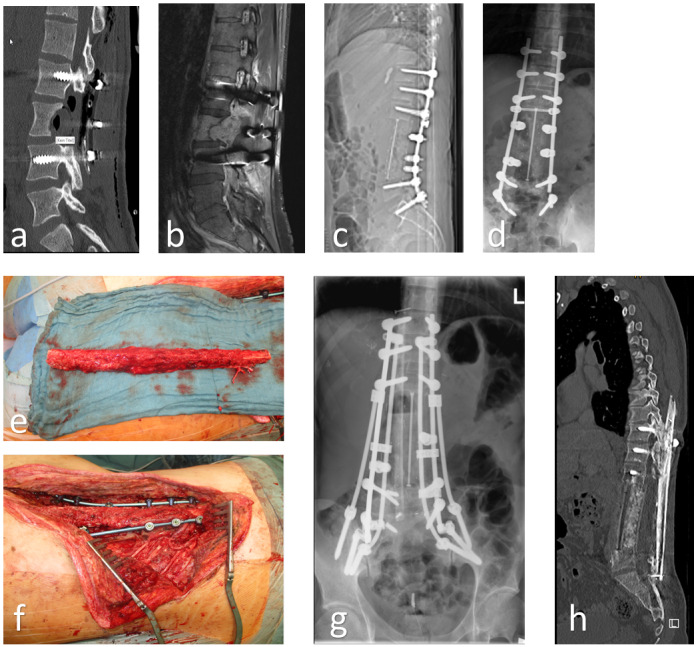

Background: Significant osseous defects or osteonecrosis, precipitated by open fractures, infections, or neoplastic conditions, represent infrequent yet critical medical conditions. The free vascularized fibular graft (FVFG) is a challenging but straightforward, reliable surgical intervention for the reconstruction of defects across various anatomical regions. This study aims to compare, quantify, and demonstrate the FVFG's versatility. The utilization of a single- or double-barrel approach, contingent on the defect's characteristics, optimizes length conservation or enhances the stability of extensive defects.

Methods: We retrospectively evaluated patients who underwent the FVFG procedure, employing either a single- or double-barrel technique, at our medical center during the period from August 2017 to May 2023. The inclusion criterion was the presence of substantial osseous defects (bone loss in straight bone over 8-10 cm or multi-level spine resection), precipitated by trauma, neoplasms, non-union fractures or infections.

Results: Our study encompassed eight male patients, with an average age of 31 years, ranging from 10 to 56. Each patient underwent osseous resection due to osteomyelitis (n=2), tumor excision (n=4), or pseudarthrosis (n=2) resulting from previous trauma, followed by a free fibula flap as part of the FVFG procedure. When fibula was simultaneously prepared already during tumor resection (n=2), there was a significant reduction in the overall operation time. Postoperative assessment revealed that full osseous integrity without any graft failure was restored in all patients, and the same number of patients regained independent ambulatory ability. Surgical complications were observed in one patient, who exhibited wound healing post-reconstruction, all of which were rectified through subsequent surgical intervention.

Conclusion: Diverse osseous defects in complex cases can be reconstructed by using the FVFG, thereby restoring maximal reconstructive capacity, expedited union compared to non-vascularized bone, and acceptable donor site morbidity. FVFG remain a reliable solution for diverse defects. Moreover, in cases requiring complex tumor defects, careful preoperative planning and an interdisciplinary treatment are essential for successful treatment.